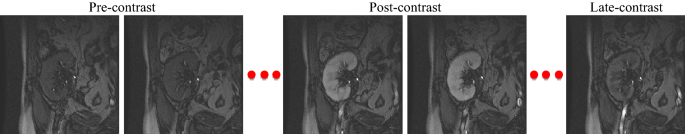

Acute rejection is the most common cause of the failure of kidney transplantation and has to be early detected to rescue the transplanted kidney1. Towards that end, one of the often used methods is DCE-MRI. DCE-MRI is obtained by injecting the patient with a contrast agent and capturing fast and frequent images for the kidney. Therefore, each patient typically has a dataset that contains a sequence of about 80 varying-contrast kidney images that are captured during the contrast agent perfusion1 as shown in Fig. 1. From these images, accurate segmentation of the kidney becomes a necessary and first step for downstream processing operations to determine the kidney status. However, it remains a challenging problem1,2 due to the low spatial resolution and contrast variation of the quickly-acquired images and motion resulting from patient breathing and movement.

A sequence of DCE-MRI time-point kidney images for one subject manifesting the contrast change caused during the contrast agent perfusion into the kidney.

DCE-MRI data is collected from 45 patients using a 1.5 T MRI scanner with a phased-array torso surface coil at Mansoura University Hospital, Egypt. All methods were performed in accordance with the relevant guidelines and regulations, and the patients’ informed consent was obtained. Our experiments were reviewed and approved by the institutional review board (IRB) at the University of Louisville. Each patient has a dataset of about 80 repeated temporal frames of size 256 \(\times\) 256 pixels in DICOM format that were obtained via injecting the patient by a dose of 0.2 ml/kgBW of Gd-DT PA contrast agent with the rate of 3–4 ml/s. The dataset contains a sequence of varying-contrast kidney images that were acquired quickly and repeatedly at 3 s intervals during the contrast agent perfusion into the kidney. A sample sequence for one subject is shown in Fig. 1. Each image was manually segmented by expert radiologists at the hospital using the Adobe Photoshop software.